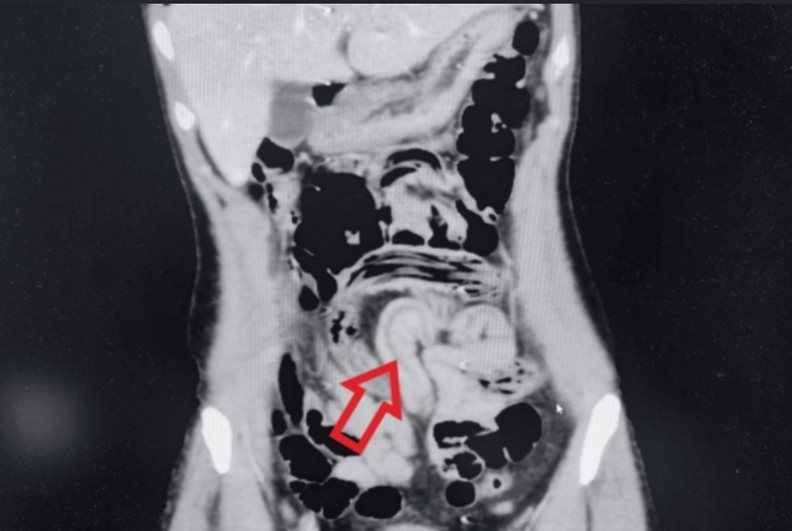

의료진은 진찰 과정에서 단순 소화불량을 넘는 복부 긴장과 압통을 확인하고, 조영제를 이용한 복부 컴퓨터단층촬영을 시행해 소장과 대장 고리 부위에 공기로 채워진 가늘고 긴 선 모양의 구조물을 찾아냈다.

영상 소견은 장 내에 이물질이 움직이고 있는 양상에 가까웠고, 의료진은 회충 감염 가능성을 최우선으로 의심하면서 충수 말단부에 생긴 염증까지 함께 확인했다.